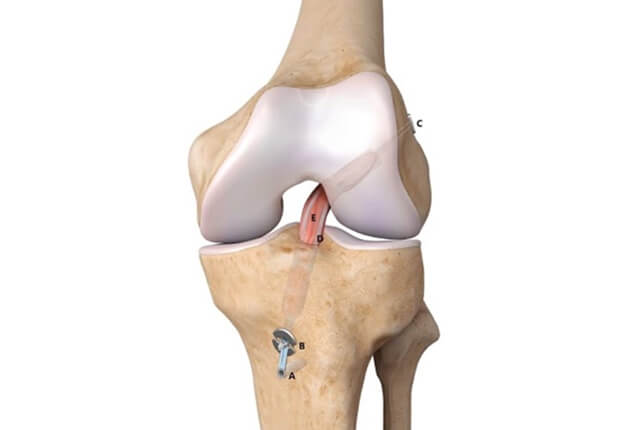

前十字靭帯(ACL)は大腿骨と脛骨をつなぐ靱帯で、後十字靭帯と交差する様に前方に存在します。

半月板は大腿骨と脛骨の間にある線維軟骨です。内側半月板と外側半月板があり、C型の形状をしています。

関節鏡視下ACL再建術

術後は理学療法を行い、およそ3ヶ月でジョギング、6ヶ月でスポーツ復帰します。